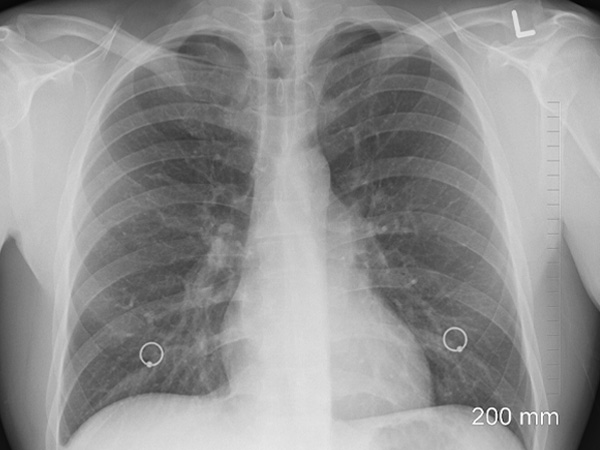

Има един златен стандарт за рак на белия дроб и това е нискодозова КТ. Какви са тези глупости и коледни инициативи на дигитални ентусиасти?!! Обърквате хората така! В настоящата ситуация и доста политици можете да объркате

Напълно споделям коментара ви! Кое отклонение в изброените показатели "ръст, тегло, индекс на телесната маса, функцията на белите дробове – спирометрия, насищането на кръвта с кислород, ЕКГ, кръвно налягане, температура.", е СИГНИФИКАНТНО за РАК на белия дроб??? КОЕ? Кажете бе, Д.Е.Б.И.Л.И?